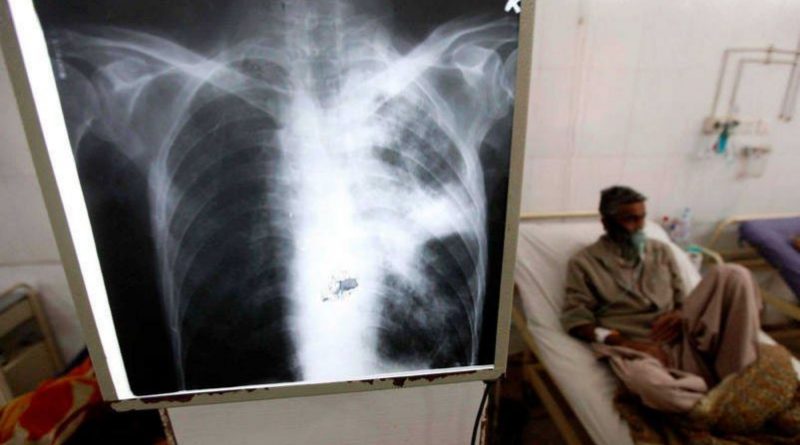

La tuberculosis es una enfermedad infecciosa que afecta a los pulmones y que es causada por una bacteria (mycobacterium tuberculosis) que se transmite de una persona a otra a través de las gotitas de aerosol que permanecen en el aire tras haber sido expulsadas por personas con enfermedad pulmonar activa.

Según datos precisados por la OMS es la enfermedad infecciosa que más muertes causa en todo el mundo: unos 1,5 millones cada año, mientras que en la Argentina, estadísticas previas a la pandemia, notificaban de unos 12.500 casos anuales, el 17 por ciento de los casos se registraban en chicos y adolescentes.